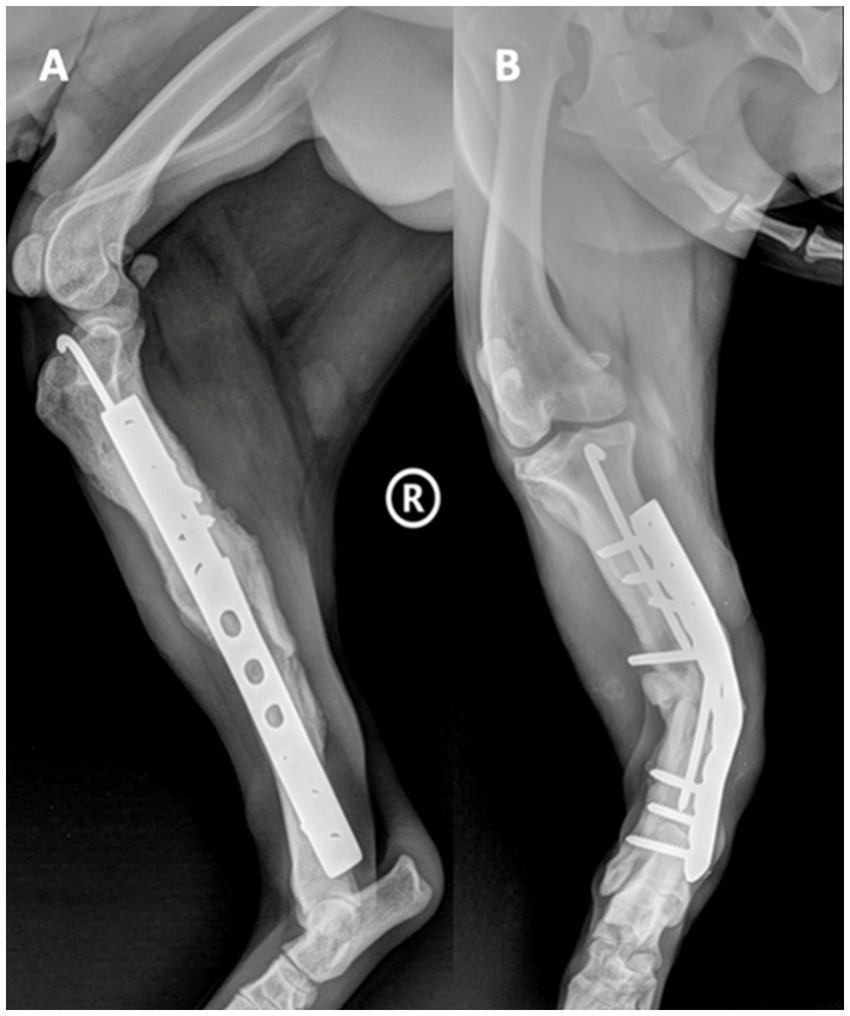

We present the case of a 3-year-old, 20-kg, mixed-breed intact male dog (BCS 5 of 9) who was referred to the Faculty of Veterinary Medicine, Cluj-Napoca, Romania, due to progressive lameness in the right hindlimb and accentuated deformity following an osteosynthesis surgery performed 4 weeks ago. After the first surgical intervention, the dog suffered a road traffic accident. He was diagnosed with an open right tibia and fibula fracture, and surgery was performed. At a surgical consultation, the dog presented a lameness score of 4 out of 5, with deformation of the limb, edema, local swelling, inflammation, heightened sensitivity, and purulent secretions. Mediolateral and craniocaudal radiographs of the right hindlimb were performed under sedation using dexmedetomidine, 0.01 mg/kg IV (Sedadex 0.5 mg/mL, Le Vet Beheer, Oudewater, Netherlands) and ketamine 3 mg/kg IV (Narkamon Bio 10%, Bioveta, Ivanovice na Hane, Czech Republic). On craniocaudal radiological exposure of the right hindlimb at the tibiotarsal region, the diaphysis of the tibia shows vicious callus, most likely result from postoperative refracture; a well-defined osteolysis zone at the middle level of the tibial diaphysis; visible orthopedic fixation elements at the level of the tibia, with a metal rod (intramedullary pin) consisting of two pieces—most likely due to the initial pin breaking into two pieces—which are correctly framed at the intramedullary level, with the tip not mobilizing the femoral-tibial-patellar joint; and the metal plate shows major unevenness due to lateral bending, while the proximal and distal locking screws remained without damage and secured the bone (Figure 1).

Figure 1. Mediolateral (A) and craniocaudal (B) radiological exposure of the right hindlimb, tibiotarsal region.